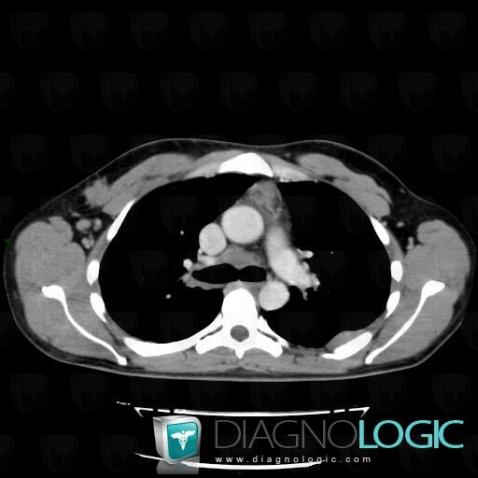

Voici les informations spécifiques à l'image clé ci dessus:

- Diagnostic Lymphome , Localisation(s) Médiastin, comportant les gammes Masse médiastinale de faible densité, Masse médiastinale moyenne